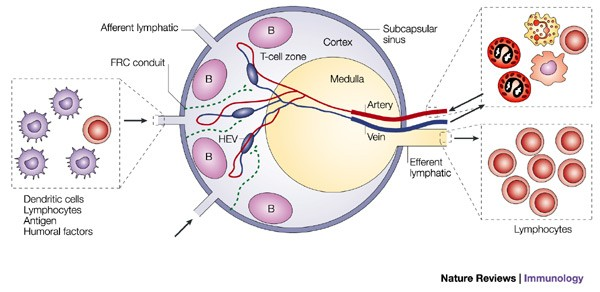

Lymph node

High endothelial venules

- 看管淋巴細胞進入血管